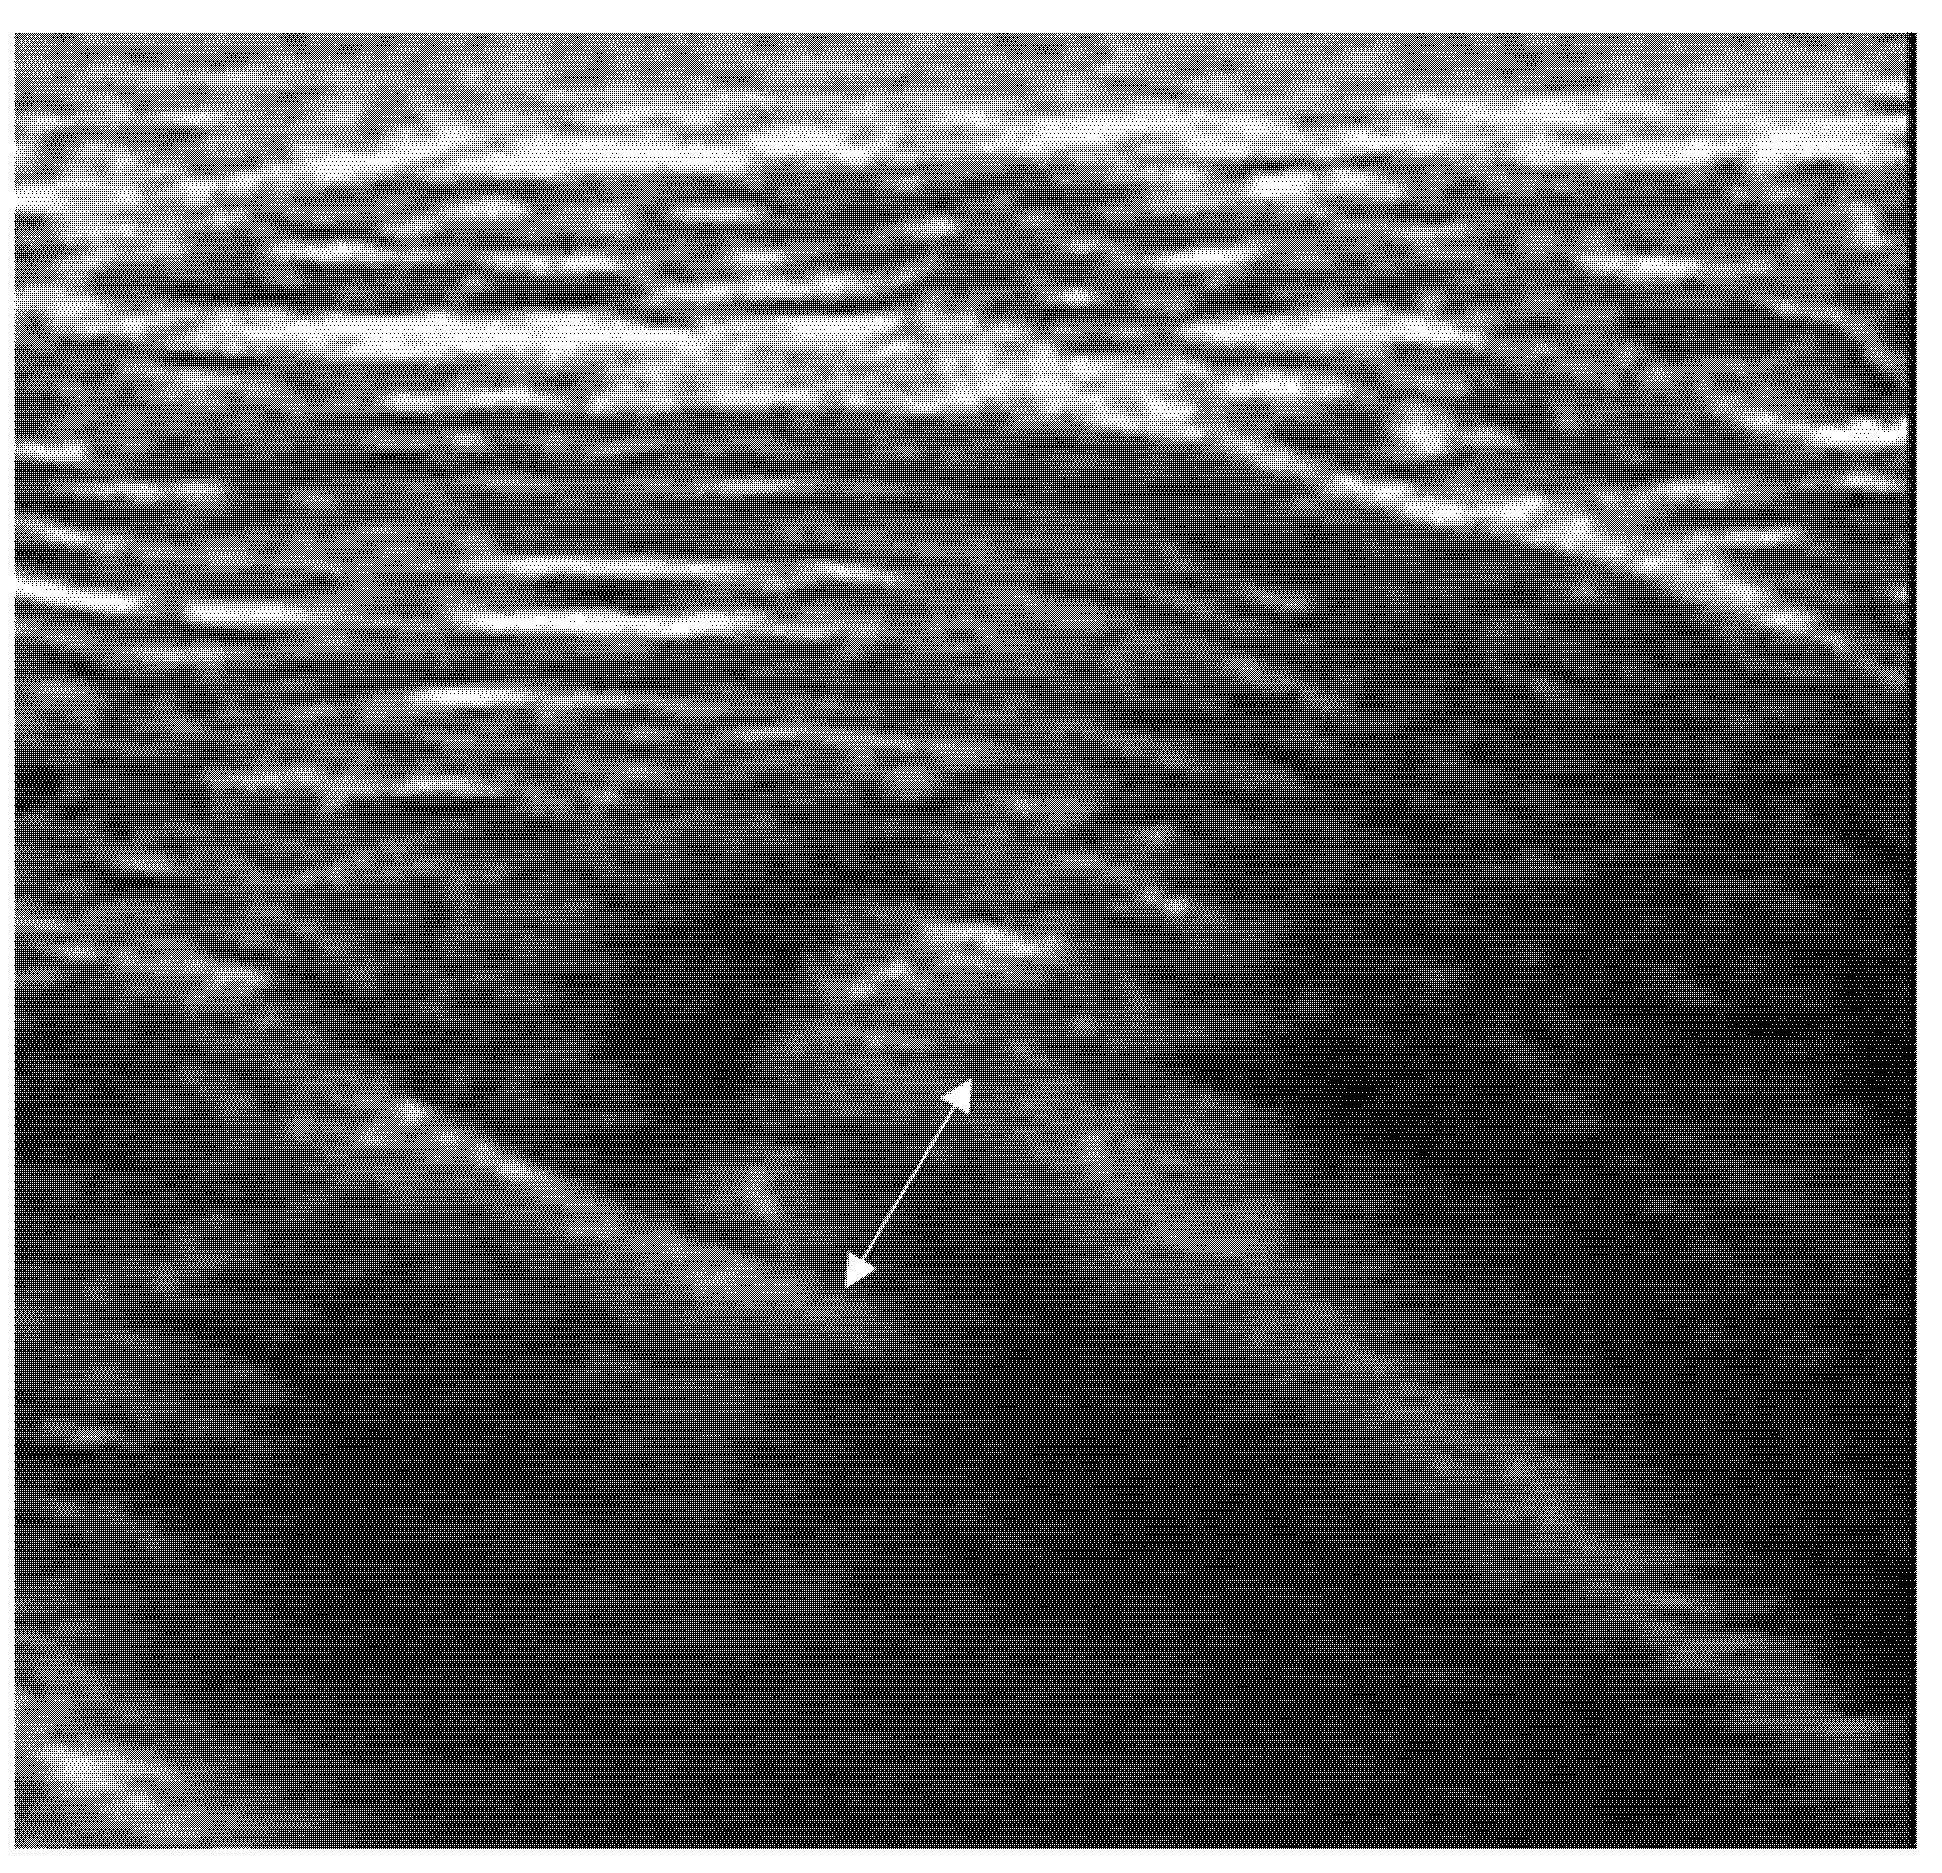

4.2. Sonoanatomy of Fractures [Figure 5, Figure 6, Figure 7 and Figure 8]

- Irregularity, interruption, or gaps in the cortical line: the cortical bone normally appears as a continuous, bright echogenic line, which is interrupted or irregular in the presence of a fracture.

- Reverberation artifacts within or adjacent to the fracture gap (also known as the “chimney sign”): these repetitive echoes are caused by ultrasound waves reflecting off the fracture surfaces.

- Bulging or abnormal angulation of the cortical layer: deformities or outpouchings of the normally straight cortical surface indicate displacement or bending at the fracture site.

- Local hematoma or soft tissue edema: fluid collections or increased echogenicity near the fracture site indicating bleeding and inflammation.

- Periosteal thickening or elevation: the periosteum may appear thickened or lifted due to injury or early callus formation.